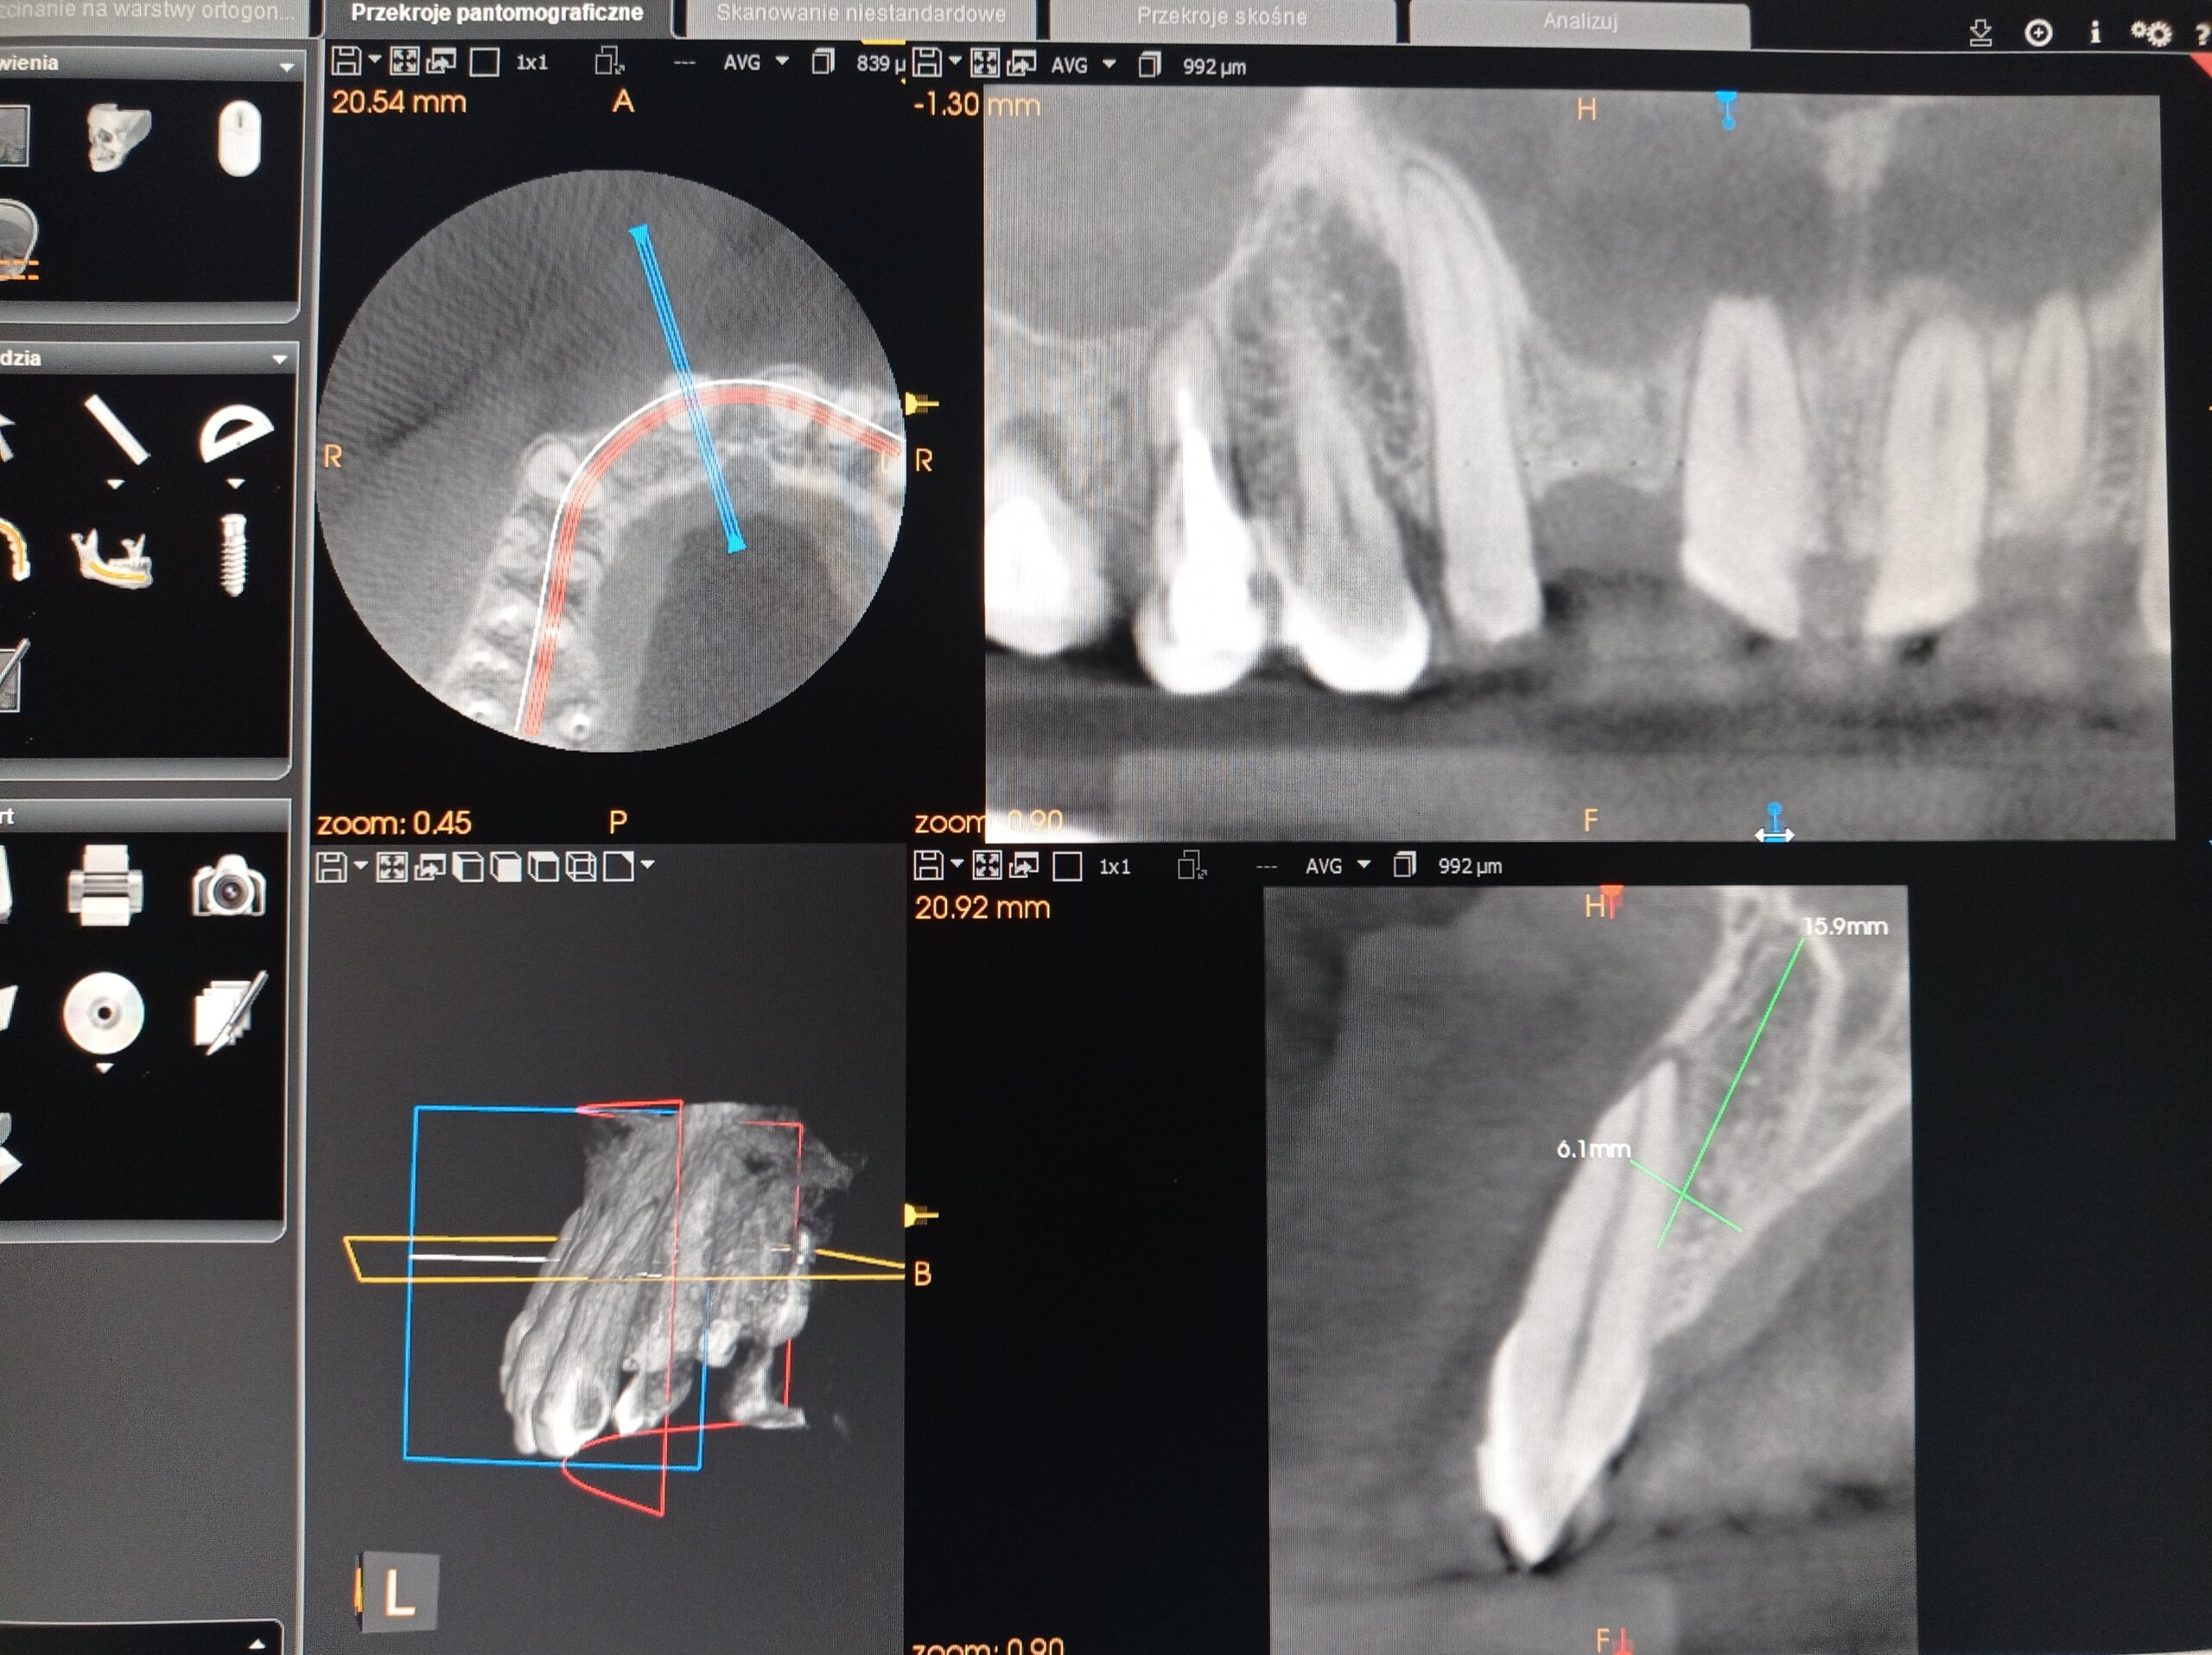

Konsultacja zawierała analizę Cyfrowego Planu Leczenia, którym był leczony pacjent. Na dodatkowe zlecenie lekarza przeprowadzono częściową analizę badania CBCT, zdjęcia panoramicznego, cefalometrycznego oraz zdjęć fotograficznych wewnątrzustnych przed i po leczeniu.

Wykonano ewaluację zaproponowanych sekwencji ruchów zębowych w dostarczonym planie 3D. Wzięto pod uwagę liczne przyczyny mogące doprowadzić do dehiscencji kostnej w omawianej okolicy, jak również przeanalizowano możliwość jej obecności jeszcze przed podjęciem leczenia. Odpowiedziano na wszystkie pytania dentysty w formie pisemnej oraz ustnej.

Wybrane ryciny z konsultacji